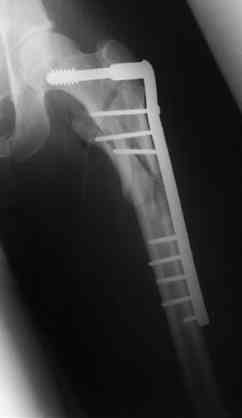

Бедро фиксировал длинной DCS.

По типу бриджинг плэйтин, крюком удалось низвести малый вертел и фиксировать винтом для восстановления медиальной стенки.

В приложении отправляю послеопер. снимки бедра и лодыжки обсуждаемого вчера больного.